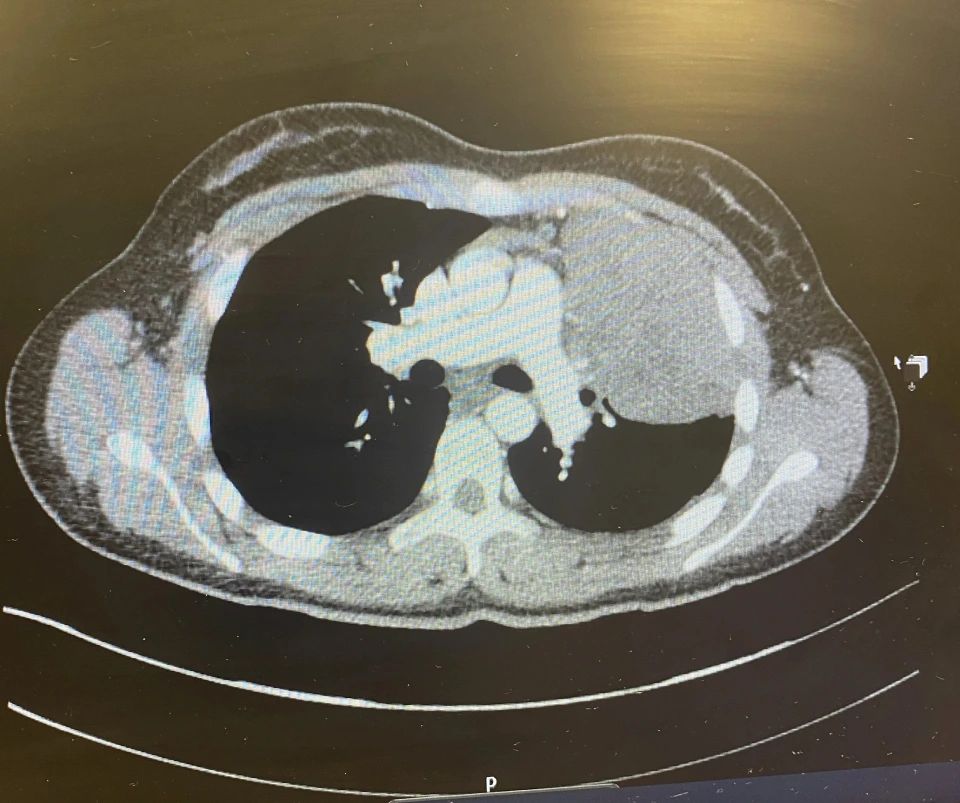

ومع تفاقم الأعراض وظهور علامات جديدة مثل ألم الظهر والصدر، طلب منها الطبيب الخضوع للآشعة السينية، ومن خلال الخضوع لإجراءات الكشف والفحوصات الطبية، تبين أنها مصابة بسرطان الغدد الليمفاوية كبير الخلايا البائية والذي يؤثر على الجهاز المناعي، بالإضافة إلى وصول الخلايا السرطانية إلى ثلاثة أرباع رئتها، وأخبرها الطبيب المعالج أنها في المرحلة الرابعة من الورم وهذا ما يعني انتشاره إلى أجزاء أخرى من الجسم.